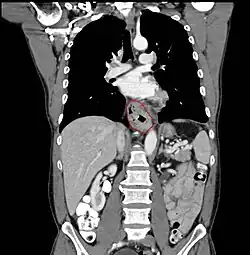

- Lower thoracic esophagus and EG junction:

- Inferior pulmonary veins to the stomach; includes the intraabdominal portion of the esophagus

- By endoscopy, 30 to 40 cm

- For cancers arising near the EGJ, they are staged as esophageal/EGJ if the epicenter is in the lower thoracic esophagus, the EGJ, or within the proximal 5 cm of the stomach (cardia) and extend into the EGJ or esophagus

- Those with an epicenter in the stomach greater than 5 cm distal the EGJ, or those within 5 cm of the EGJ but that do not extend into the EGJ or esophagus, are staged as gastric

- Siewert classifaction is disregarded

- GE junction: (Classification by Siewert: PMID 11525305, PMID 9823902), center within 5 cm proximal/distal to GEJ

- Type I (distal esophagus) - arises from area with specialized intestinal metaplasia of the esophagus. Commonly, center of the tumor located 1 - 5 cm above the gastroesophageal junction

- Type II (cardia, considered gastric) - arises from the cardiac epithelium or short segments with intestinal metaplasia at the GEJ. Commonly, center of the tumor located 1 cm above to 2 cm distal to GEJ

- Type III (sub-cardia, considered gastric) - arises from subcardial location and infiltrates GEJ from below. Commonly, center of tumor >2 cm distal to GEJ